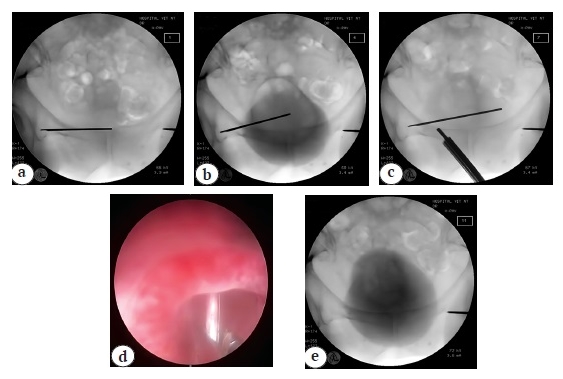

Fig. 3. X-rays of the pelvis in AP (a) and axial (b) views: K-wire is located in the area of left femoral head and acetabulum; the wire is removed from the joint cavity (c); removed foreign bodies 4 and 10 cm long (d)

The patient was put on the right side, the ope-rative field was treated, and Harding approach to the left hip joint was performed. After removal of the femoral head, the wire fragment was found in the joint cavity and was removed (Fig. 3 c, d). Cemented left hip arthroplasty was performed (Fig. 4).

Fig. 4. X-rays of the pelvis in AP (a) and axial (b) views after wire removal and total left hip replacement